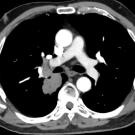

Alexandra Close, BS; Maaria Chaudhry, MS; Kirill Alekseyev, MD; Bilal Chaudhry, MD

A 60-year-old woman presented to the emergency department with blunt thoracic trauma after a head-on motor vehicle accident.